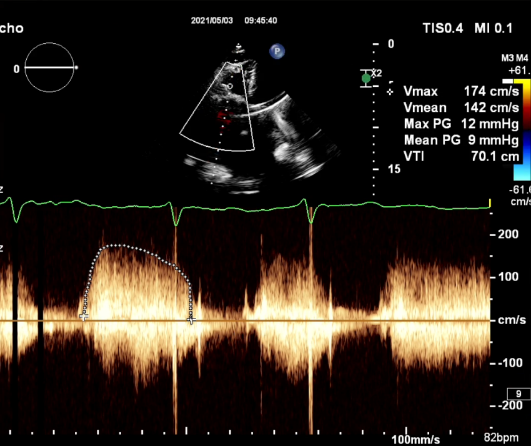

食道超声评估

三尖瓣术前平均压差9mmHg

三尖瓣瓣中瓣术后平均压差3mmHg